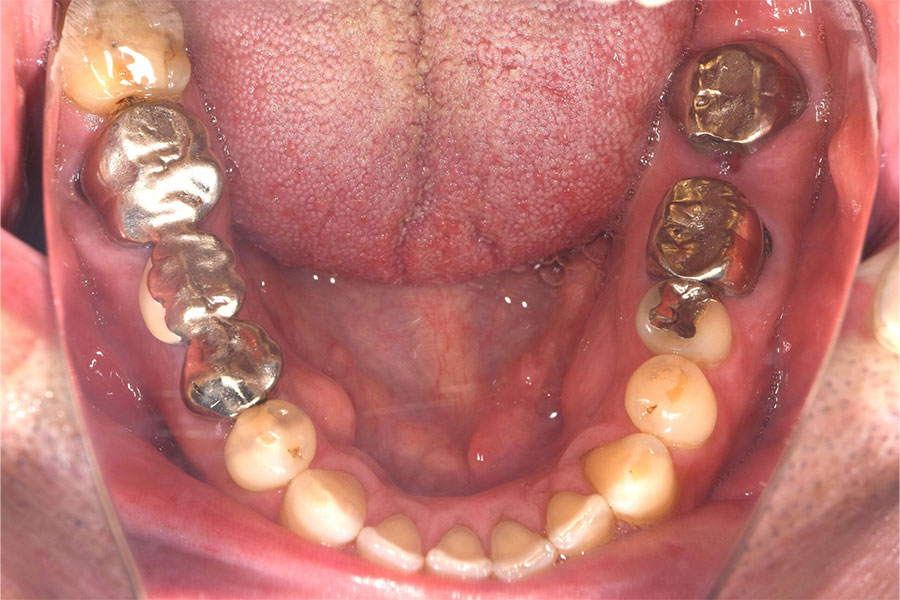

原因となる

金属の除去、置換

皮膚科で行うパッチテストでは、患者様の体がどの金属にアレルギー反応を起こすのかを検査します。口の中に使われている金属に陽性反応が示された場合、その詰め物や被せ物、入れ歯を除去するか使用をやめます。さらには、金属アレルギーの心配がない、患者様の体質に合った歯科材料による修復・交換治療を行います。

ただし、陽性反応が示された場合であっても、その原因のみを除去することで全ての症状がなくなるとは限りません。原因の除去で改善することが多い金属アレルギーですが、複数の物質が原因となっている場合や環境によって引き起こされる場合もあります。